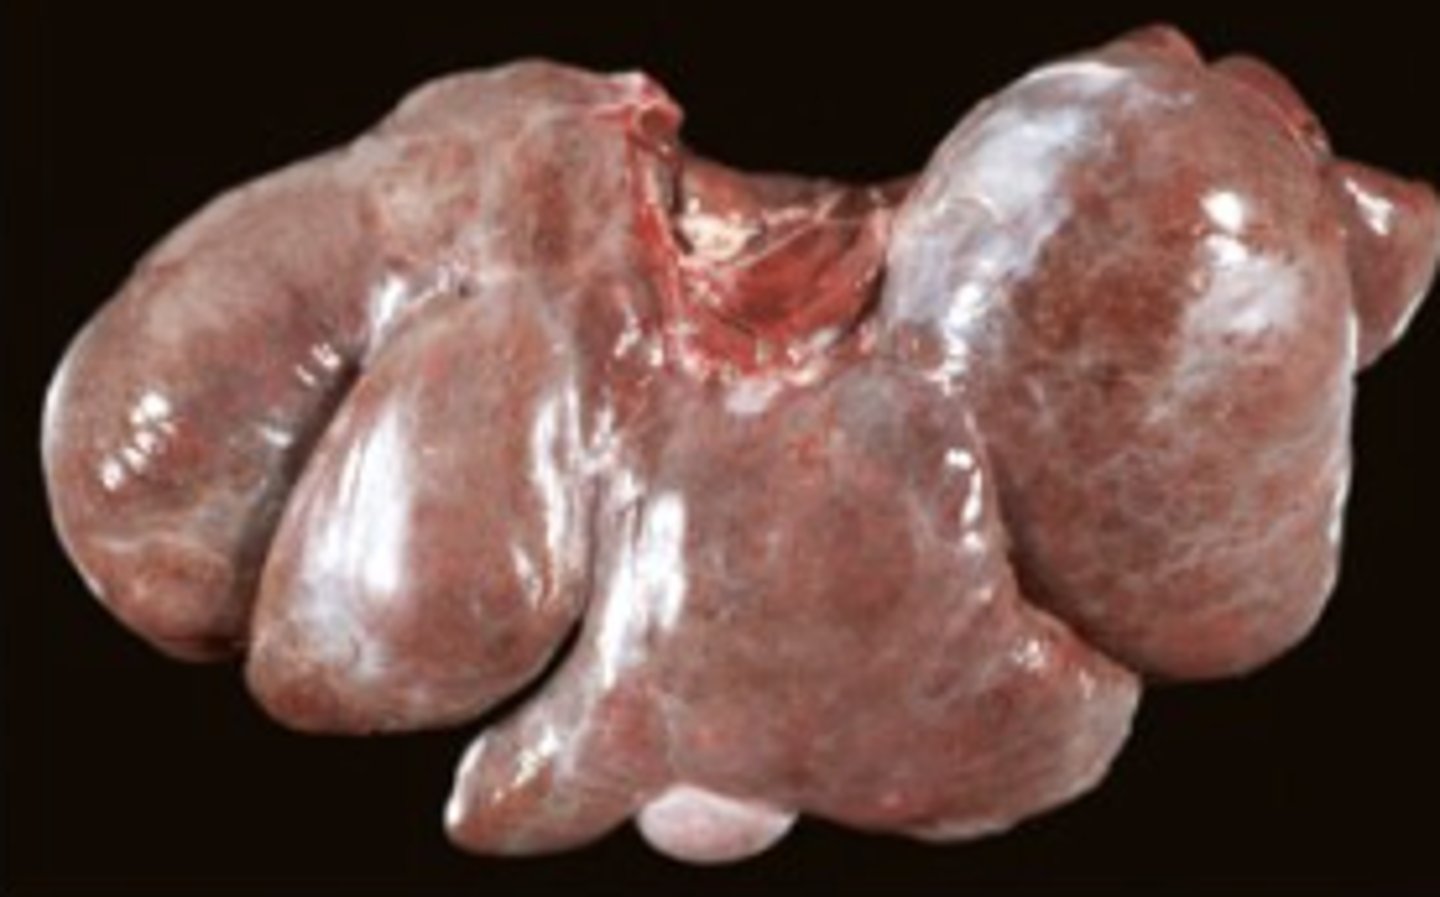

spleen, diffuse enlargement, rounded edges, mottled red color

splenomegaly - splenic lymphoma

Describe this lesion + diagnosis